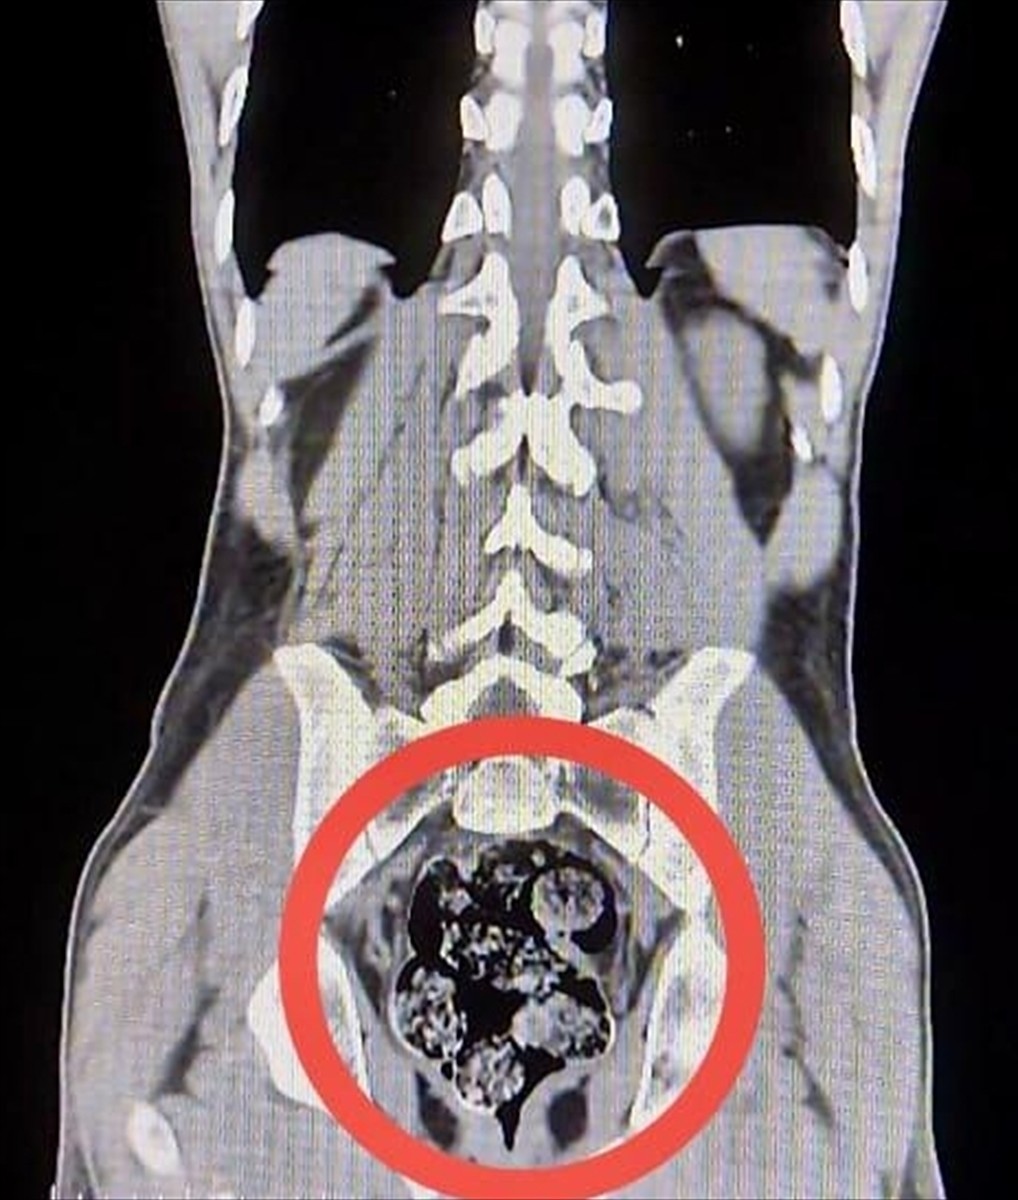

Hastanede yapılan tetkikler sonucunda, Amır Rafıeı S.'nin mide ve bağırsaklarında 7 parça halinde toplam 203,02 gram sentetik uyuşturucu tespit edildi. Uyuşturucu cerrahi müdahale ile çıkarıldı.